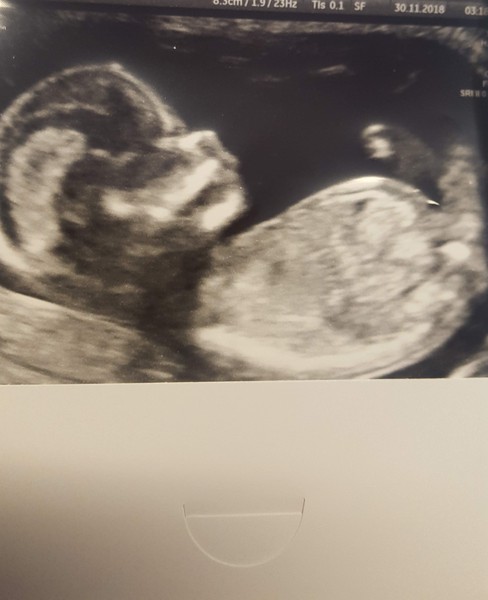

Got another photo fri bit clearer i think must be cos different machine

@swisbet lovely scan photos. Good to be moved forward a bit more too. How are you feeling now?

@Swisbest2 Aw lovely scan pic. Really good picture. You feeling calmer.